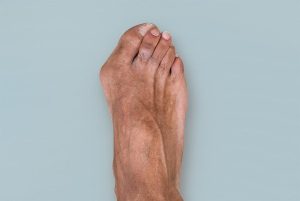

🦴 Lisfranc Injury (Midfoot Fracture) Treatment in Ahmedabad, Rajkot & Surat

By Dr. Ankit Kamothi – Foot & Ankle Specialist in Gujarat 🦴 Lisfranc Injury (Midfoot Fracture) Treatment in Ahmedabad, Rajkot & Surat By Dr. Ankit Kamothi – Foot & Ankle